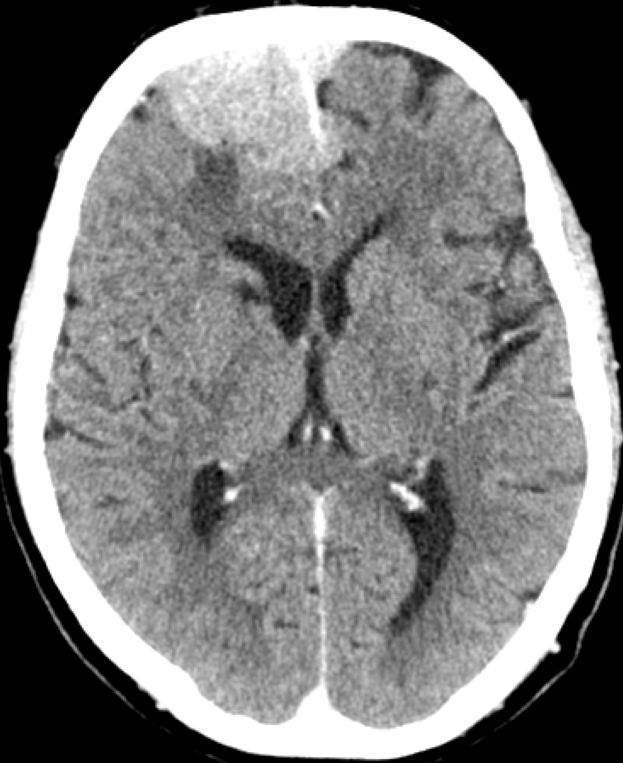

Klinik Scharf begrenzt, homogen, extraaxiale Raumforderung. Breite Verbindung zur Dura. Nach KM homogenes Enhancement. 20% Verkalkungen oder Schädelveränderungen (Hyperostose, Osteolyse). Wenn alle Kriterien erfüllt sind, ist eine histologische Sicherung entbehrlich.

Diagnostik Fallbeispiele